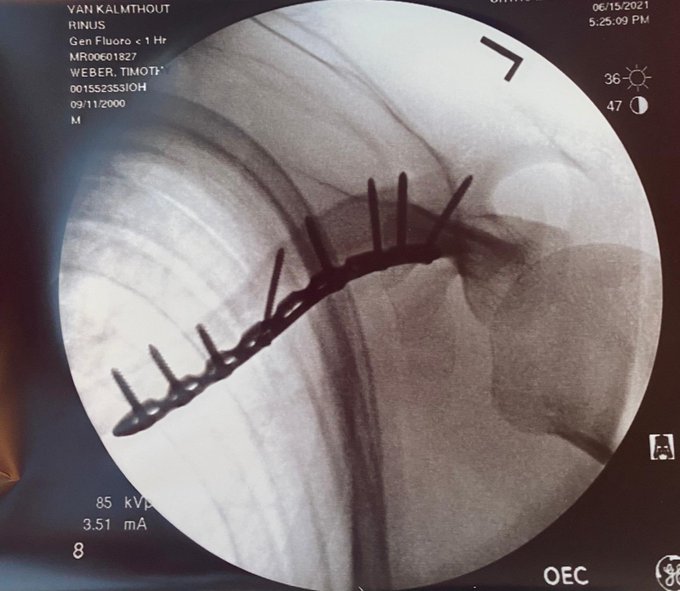

Door zijn ongeluk kan Veekay de aankomende race op Road America niet meedoen. Op 4 juli volgt een evaluatie om te kijken of Van Kalmthout weer kan starten. In zijn tweet wenst de Nederlander zijn invaller, Oliver Askew, veel succes. Ook laat hij een foto zien van de pinnen in zijn sleutelbeen.